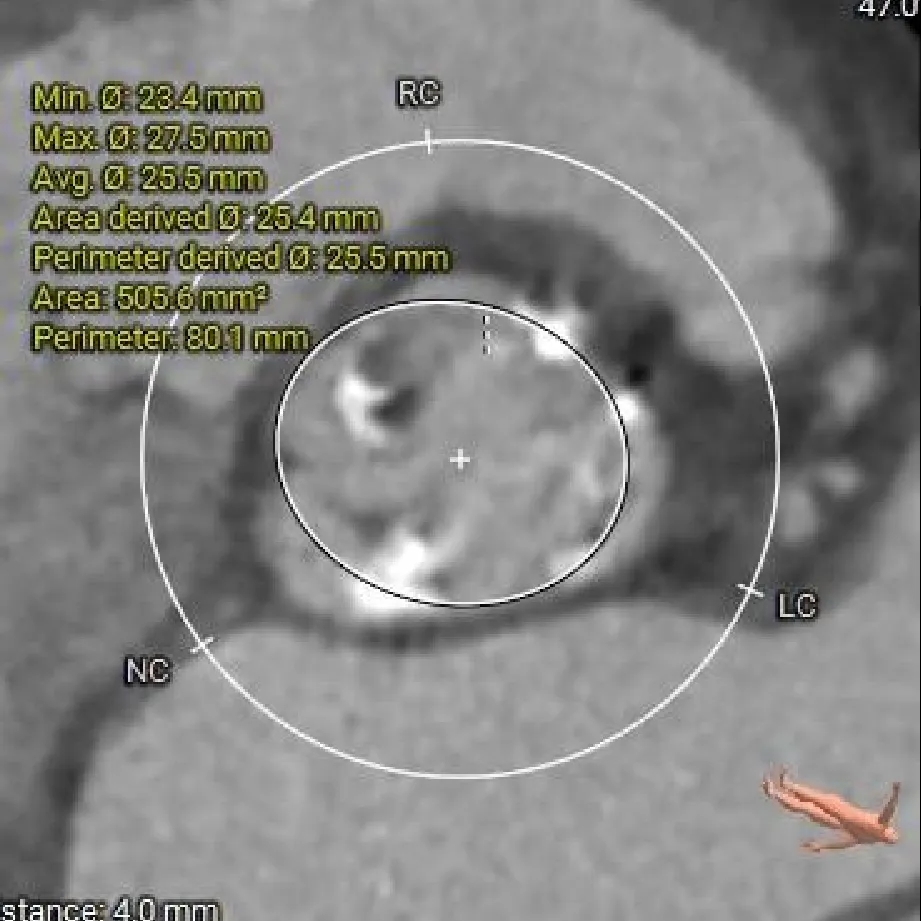

瓣上 2mm

24.7mm

瓣上 4mm

25.5mm